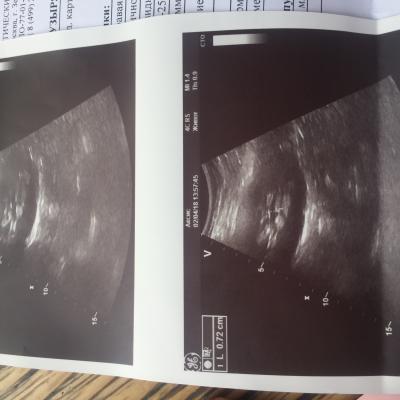

Здравствуйте. С Рождения гидронефроз левой почки , была удалена в декабре 2009 года. Анализы мочи и биохим анализ крови все показатели всегда в норме. Ребёнку 8 лет, сейчас одно УЗИ показывает размер почки 112 на 56, лоханка 16 мм. Другое узи сделанное через день показало: размер почки 78 на 30 , лоханка 7 мм. Паренхима на обоих узи 13 мм. Так же было сделано исследование УЗДГ почки ( все в норме, отклонений нет) Не можем понять почему такая разница по УЗИ где правда ? Как нам с этим разобраться .